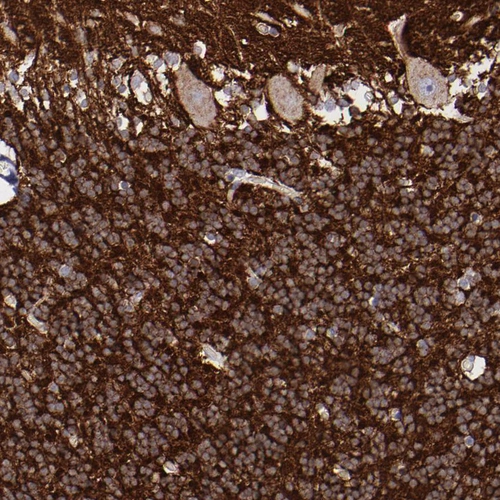

Immunohistochemistry analysis in human cerebral cortex and testis tissues using HPA001830 antibody. Corresponding SNAP25 RNA-seq data are presented for the same tissues.